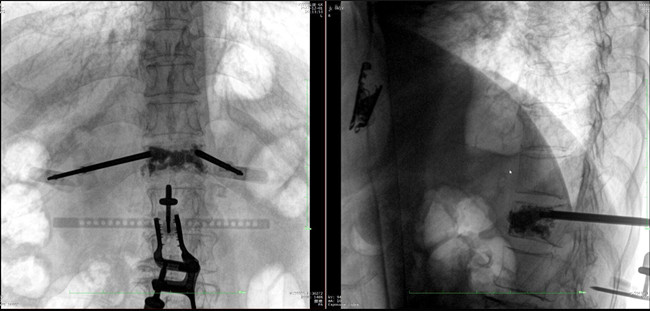

步驟二:手術(shù)實(shí)施

在病人體表切開一個長1-2cm的創(chuàng)口,沿骨科機(jī)器人的機(jī)械臂定位點(diǎn)方向?qū)⒖耸厢槍?dǎo)向套筒,通過創(chuàng)口送至病灶椎體處,并沿套筒方向打入克氏針進(jìn)行定位。沿導(dǎo)針插入工作套管,取出導(dǎo)針,完成球囊擴(kuò)張后,通過骨水泥注入器準(zhǔn)確地在骨折部位緩慢注入骨水泥,幫助其恢復(fù)椎體的形狀和強(qiáng)度。

? 手術(shù)效果確認(rèn)

*骨水泥置入效果良好